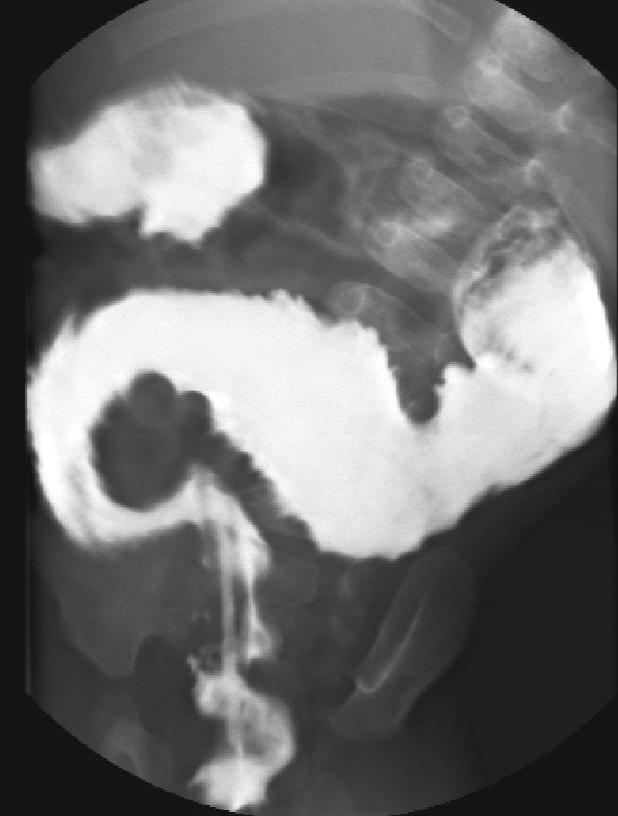

Hirschsprung-disease. In this disease the ganglions of the distal colon are missing. The lack of innervation of the colonic smooth muscle results in spastic functional obstruction. The symptoms can appear right after birth with the lack of meconium defecation and signs of obstruction. On plain abdominal X-ray the proximal intestines are distended with or without air-fluid levels, the distal loops are gas free. With contrast enema the distal, irregular, spastic, non-innervated segments and the proximal prestenotic dilatation of the colon can be visualized.

Image

21. The distal segment of the colon is narrow, irregular (aganglionar segment). Transitional zone (arrow) and compensatory prestenotic dilatation. Hirschsprung-disease.